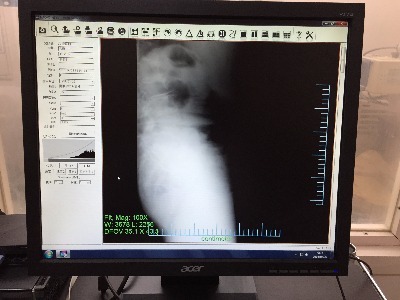

放射線のリスクがあるからこそ、医師もレントゲン撮影による精密検査を勧めません。

しかし、痛みがつづくようなら骨折、脱臼している場合もあるので、レントゲンで原因を突き止めましょう。

どうしてもレントゲン撮影が必要な場合は、ふじた医院では放射線被爆の少ないデジタルレントゲンを使用しています。